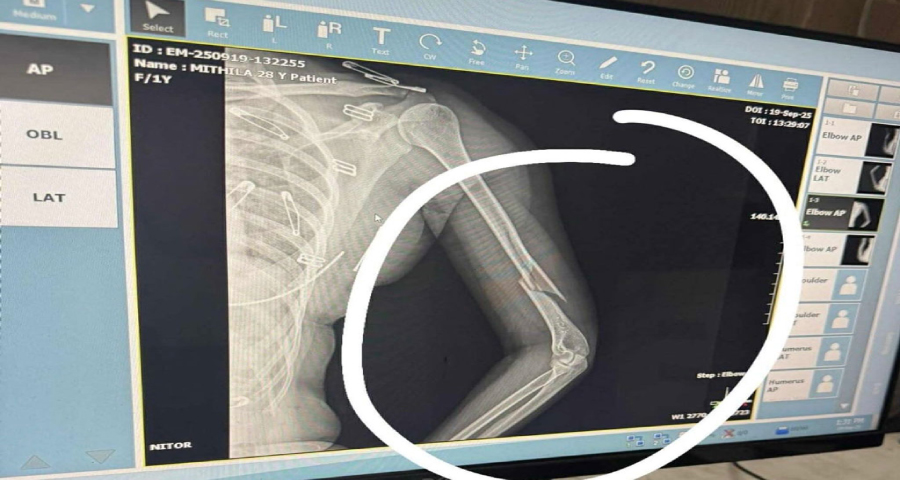

এক্সরে পরীক্ষায় দেখা গেছে, তার বাম হাতের কনুইয়ের ওপরের (বাহু) হাড় ভেঙে অনেকটা আলাদা হয়ে গেছে।